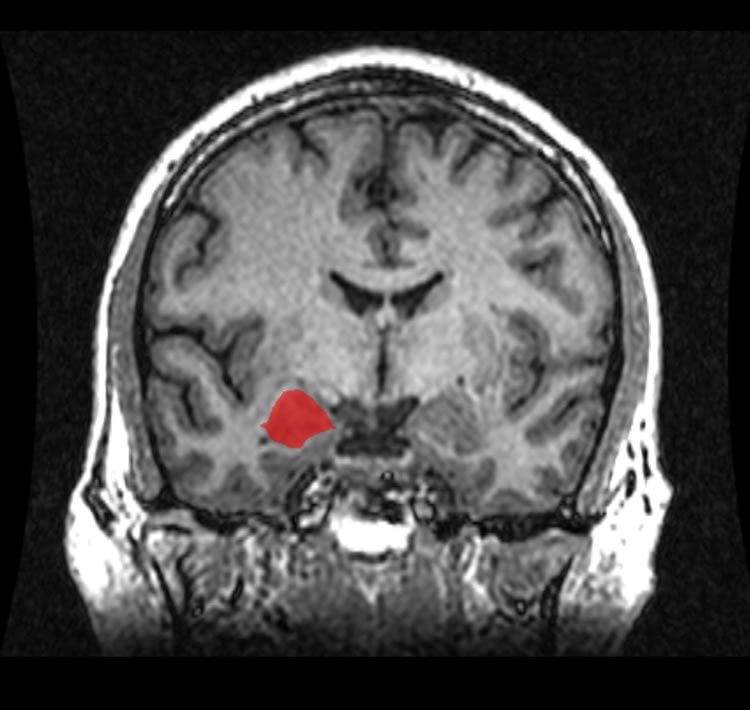

The researchers found that subjective ratings of negative images were higher in women compared to men. Higher testosterone levels were linked to lower sensitivity, while higher feminine traits (regardless of sex of tested participants) were linked to higher sensitivity. Furthermore, while, the dorsomedial prefrontal cortex (dmPFC) and amygdala of the right hemisphere were activated in both men and women at the time of viewing, the connection between the amygdala and dmPFC was stronger in men than in women, and the more these two areas interacted, the less sensitivity to the images was reported. “This last point is the most significant observation and the most original of our study,” said Stéphane Potvin, a researcher at the Institut universitaire en santé mentale and co-author of the study.

The amygdala is a region of the brain known to act as a threat detector and activates when an individual is exposed to images of fear or sadness, while the dmPFC is involved in cognitive processes (e.g., perception, emotions, reasoning) associated with social interactions. “A stronger connection between these areas in men suggests they have a more analytical than emotional approach when dealing with negative emotions,” added Potvin, who is also an associate professor at the University of Montreal’s Department of Psychiatry. “It is possible that women tend to focus more on the feelings generated by these stimuli, while men remain somewhat ‘passive’ toward negative emotions, trying to analyse the stimuli and their impact.”

Image Source: The image is credited to the Amber Rieder, Jenna Traynor, & Geoffrey B Hall and is in the public domain